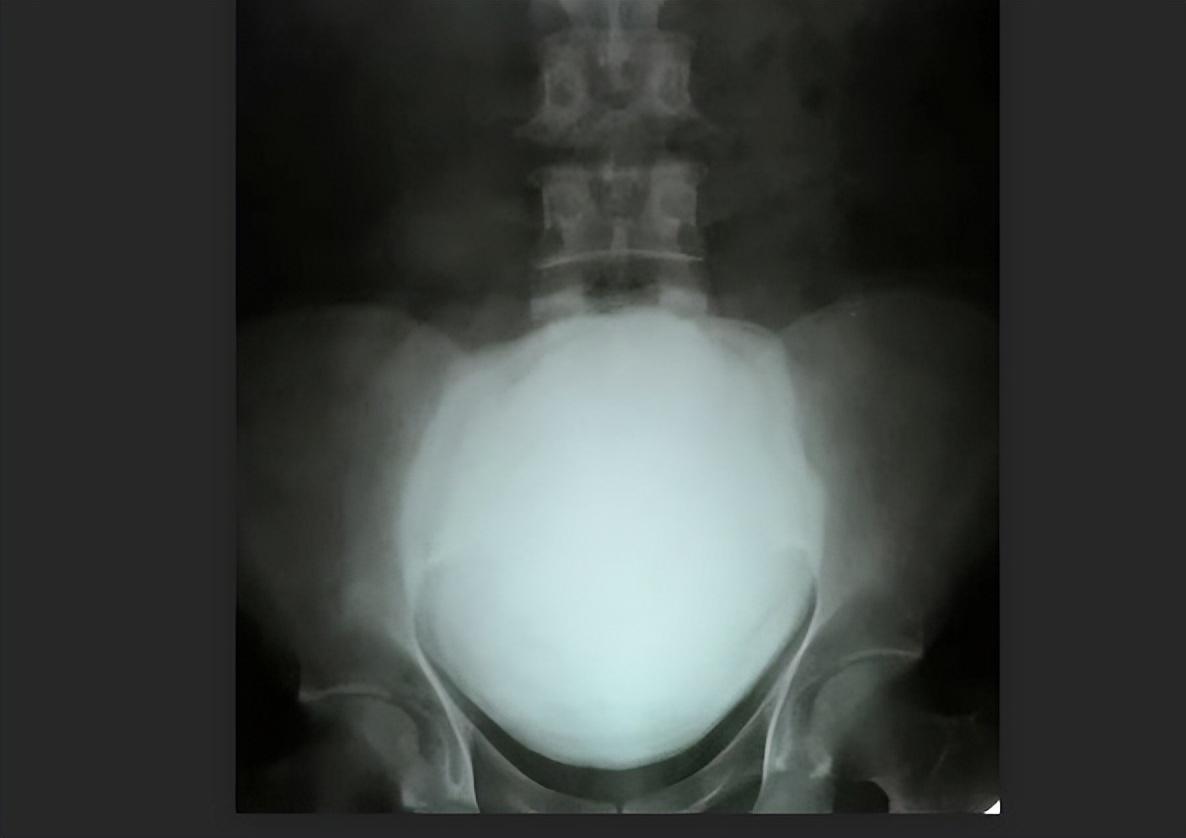

2023年6月14日周三,斯里兰卡军方官宣,该国军医已经从一名62岁的退役士兵体内切除了目前被吉尼斯世界纪录认证的世界上最大的肾结石。

消息称 ,从前中士卡尼斯图·孔吉体内取出的巨大肾结石最大长度达13.37厘米,比普通人肾脏轴向10至12厘米的长度还要长;结石重达801克,则是普通男性肾脏重量的5倍以上。

斯里兰卡军方在一份声明中说:“6月1日,科伦坡陆军医院进行了一次大手术,取出了世界上最大最重的肾结石。”

据患者自述,自从2020年以来他一直腹痛,口服了一些药物都无济于事。在最近进行的一次扫描后,被诊断出巨大肾结石,需要接受手术治疗。

吉尼斯世界纪录官网已经对这一创世界纪录的巨大肾结石进行了认证:结石最大长径13.372厘米,

于2023年6月1日在斯里兰卡科伦坡的Canistus Coonghe被取出。

此前该项纪录为13厘米,重量为620克。